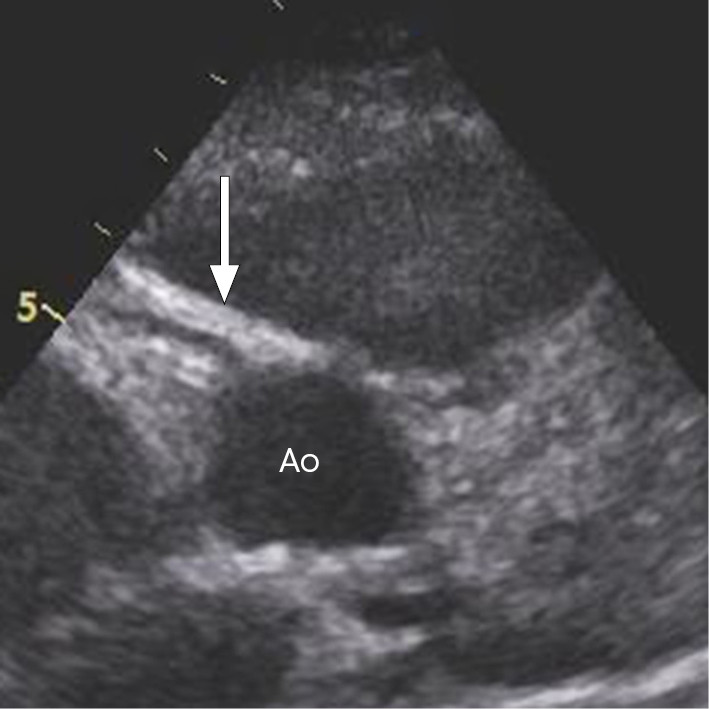

Dag 4 viste ekkokardiografi økt ekko i koronarveggen, som kan være et tidlig tegn på koronaraffeksjon (figur 1). Inflammasjonsmarkørene hadde falt fint etter første dose immunglobuliner, men feberen vedvarte. Man startet derfor med acetylsalisylsyre 500 mg × 4 per døgn peroralt. Dag 5 ble det gitt en ny ekvivalent dose immunglobuliner, hvorpå pasienten ble afebril.